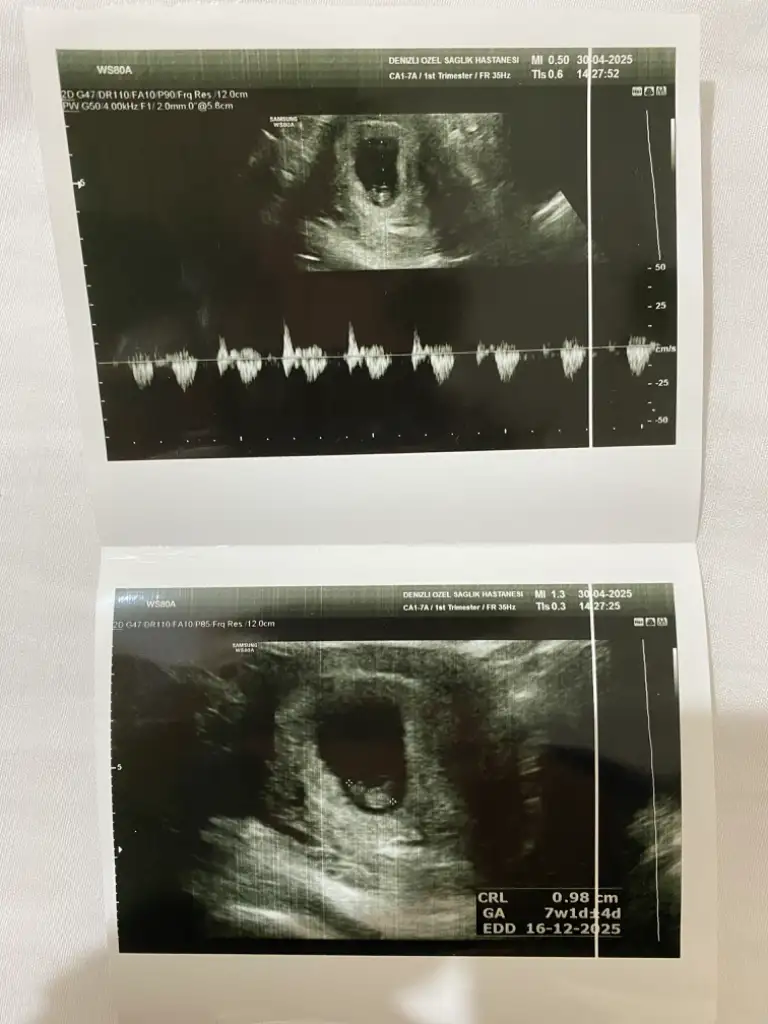

Banada bakabilir miisniz görsel olarak yorumlara ekledim :) ilk görsel 10+4 diğer görseller 6+4 haftalıkken karından ultrasonla bakıldı

Pek anlamıyorum ama kendim için araştırmaya girdim kaç gündür araştırmalarıma göre kız gibi geldi banaBana da tahminde bulunabilir misiniz kızlar 10. Hafta goruntumden

Merhaba nub teoremine gore kiza benzettim ben ama rabbim go lunuze gore versin insallahBana da tahminde bulunabilir misiniz kızlar 10. Hafta goruntumden

Sizce benimki ne olabilir ben erkeğe benzetiyorum ama eminde değilim kız diyenlerde olduMerhaba nub teoremine gore kiza benzettim ben ama rabbim go lunuze gore versin insallah